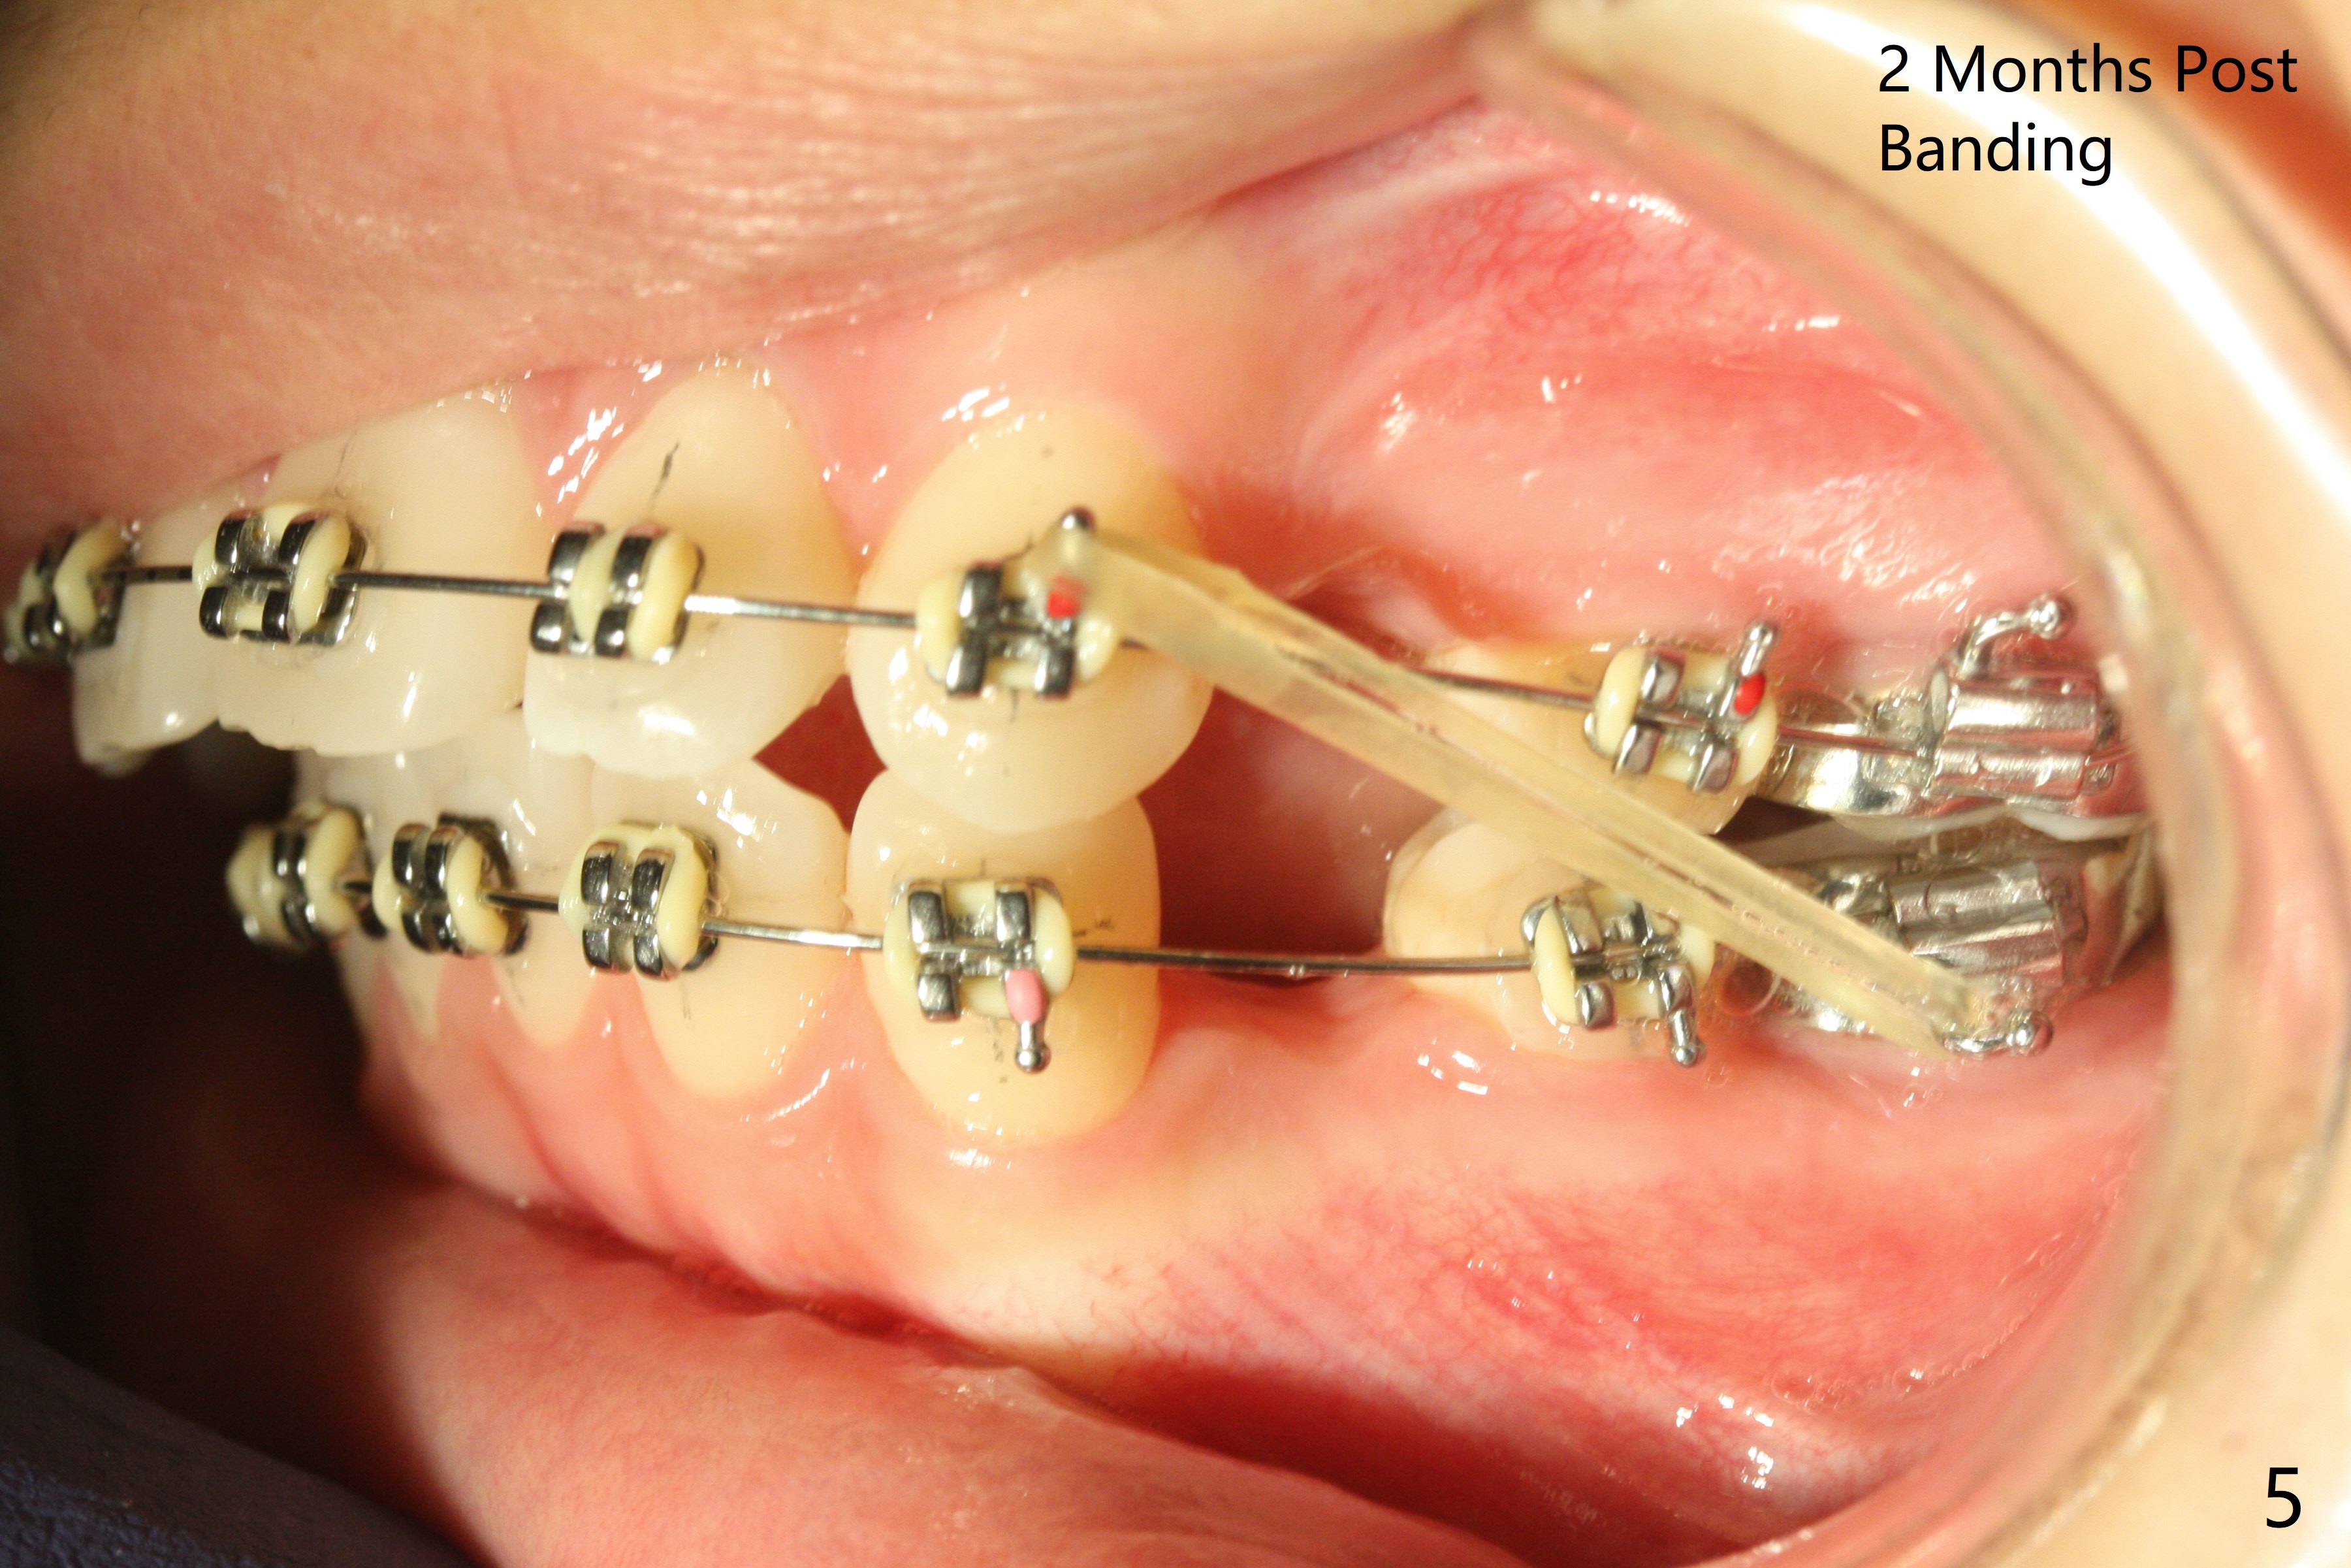

Two weeks post extraction of 4 bicuspids, brackets and bands are placed in 20 teeth (Fig.1-3, 14 niti). No bands are placed at 7s because of short crowns and tight contacts. When 16x16 wires are used, start Class II retraction. The latter is initiated with elastics when 18 ss wires are placed (Fig.4,5). U3s have been distalized with closed springs for 3 months (Fig.6,7). U2s are close to distalization 13 months post banding, 3.5 months post posted wire (Fig,8,9) with overjet (Fig.10). Class II retraction is re-initiated. When the upper incisors are retracted, the anterior overjet remains large. It appears that U6s have been retracted anterior, as indicated by the space between U6/7 (Fig.11), because of no use of U7s as anchors. Brackets are just placed with 18 niti arch wire. They will be retracted distal using the rest of the upper teeth and lower teeth (using Class II retraction) as anchor. There is root resorption of the upper anteriors 2 years 1 month post banding (Fig.12,13).